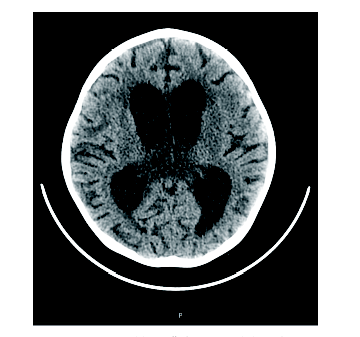

周正根(影像科主治医师):根据患儿的影像学图片介绍一下TBM的影像学特点, 首先, TBM比较容易出现脑积水, 见图1, 在脑底部的脑池可见分泌物, 脑室壁增厚; 其次, 脑室、脑沟可见到钙化, 见图2和图3, 钙化灶对结核的诊断有一定意义; 第三, 由于TBM可能侵犯到小血管, 所以可以见到一些低密度的梗塞病灶。

患儿确诊TBM, 治疗上继续三联抗结核治疗及鞘注抗结核药物。但后续治疗过程中患儿再次出现呕吐, 伴右侧肢体抖动、意识改变、双侧瞳孔不等大, 神志淡漠, 头颅CT平扫检查提示交通性脑积水, 双侧基底节区及左侧额叶、右侧顶叶皮层低密度灶, 考虑梗塞可能性大。遂予床边行颅骨钻孔脑室外引流术。并予甘露醇脱水减轻脑水肿。后患儿病情好转后转到胸科医院进一步专科抗结核治疗, 其间因脑积水在我院反复行左右脑室钻孔引流术, 最终行左侧脑室腹腔引流术。后患儿病情好转、稳定, 复查骨髓为完全缓解, MRD检测未见残留。遂按照GD2008广东协作组方案再次化疗, 并继续三联抗结核治疗, 其间多次查脑脊液TB-DNA定量水平均正常(10拷贝)。